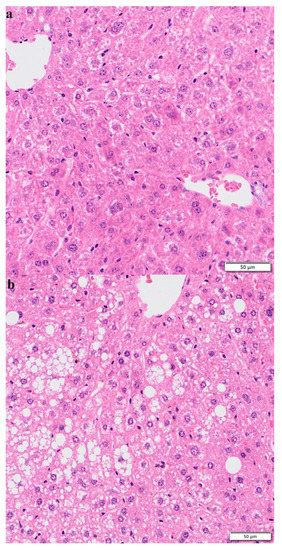

3.7. Hematoxylin–Eosin Staining